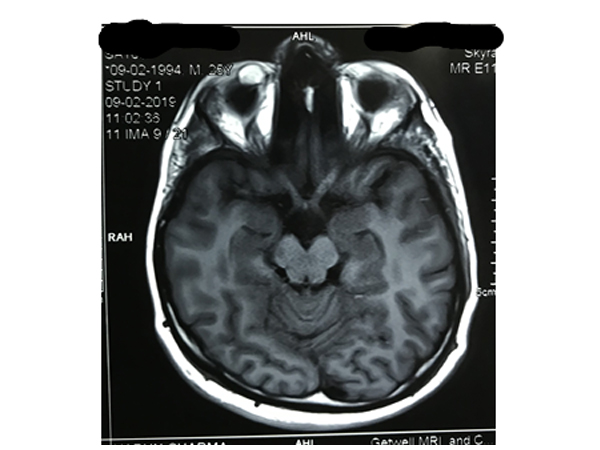

CT scan and MRI scan

These imaging modalities are required to know the pathologies that are not visible directly or their nature is ambiguous. These investigations are required in cases of

Optic Nerve disorders like Neuritis, Tumors etc.

Ocular and Extraocular tumors, cystic lesions etc.

Orbital fractures

Localization of intraocular foreign body

Inflammatory Orbital conditions like Thyroid Orbitopathy

Suspected brain involvement

Ocular Nerve paralysis